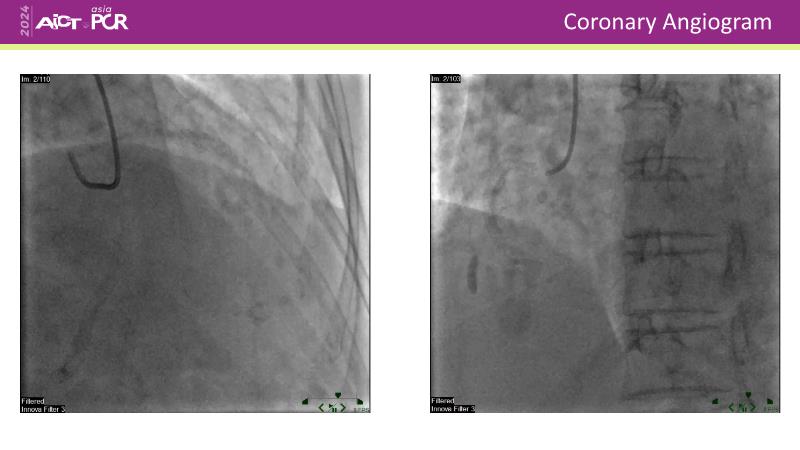

Discover the power of drug-coated balloon (DCB) technology in modern PCI. Understand the mechanism of action, including antiproliferative agents, drug transfer to the vessel wall, and effective inhibitory level and duration of vessel wall retention. Learn how IVUS can guide optimal lesion preparation, and explore the criteria for delivering effective DCB treatment.

- To learn how IVUS can guide optimal lesion preparation

- To learn the criteria for optimal lesion preparation prior to DCB application